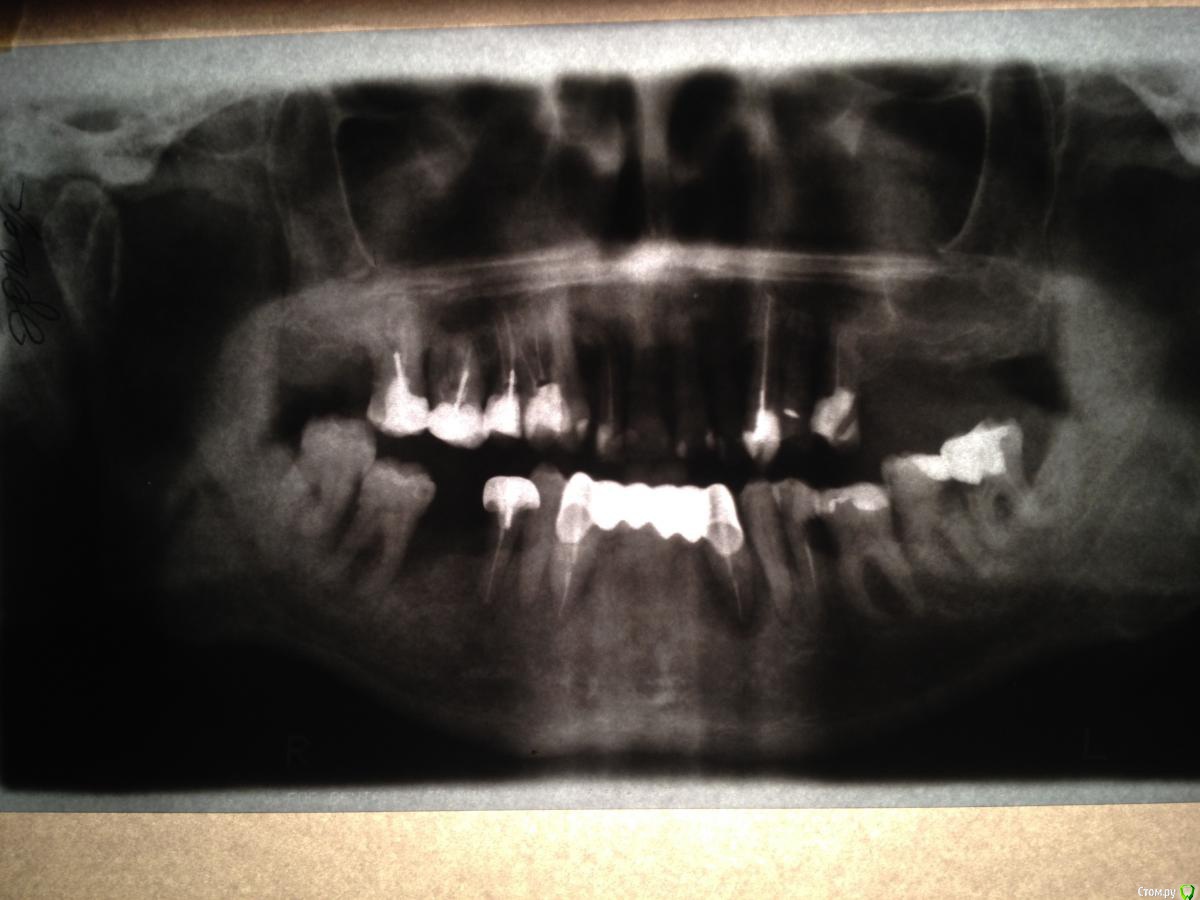

viktorr64 Опубликовано 10 марта, 2019 Поделиться Опубликовано 10 марта, 2019 Прошу совета у опытных протезистов. Начал сильно шататься мост из металлокерамики,есть подвижность в разной степени большинства зубов кроме 11 и 21, клык 13 выпирает и стоит" мертво". Консультации с несколькими врачами дают совершенно различные результаты. В областной стоматологии советуют удаление -14,13,12,11,21,22,23,38,37,33,43,44,47,48. (21 и 11 чтобы сделать красивые зубы). Хороший знакомый врач - лечить 35 ставить штифт ,удалять нервы с верхних передних зубов удалять 12(сильно шатается) и удалять мост с 44, делать верх мостами низ съемный. Еще один врач советует удалить мост ,44,12 ,37,38 и делать съемный верх и низ .Склоняюсь к третьему варианту (зубы хоть и некрасивые но свои) Прошу совета по выбору и есть ли необходимость удалять 37 38 (стоят неплохо) Какие могут быть последствия разных вариантов? Фото родных зубов могу приложить,.Очень прошу помочь.Заранее спасибо ! Ссылка на комментарий

red_butler Опубликовано 10 марта, 2019 Поделиться Опубликовано 10 марта, 2019 качество снимка не позволяет дать ответ Ссылка на комментарий

viktorr64 Опубликовано 10 марта, 2019 Автор Поделиться Опубликовано 10 марта, 2019 качество снимка не позволяет дать ответСпасибо, что обратили внимание! Выкладываю фото сделанное фотоаппаратом и фото передних зубов.P.S. В зеркале зубы выглядят лучше , надеюсь аппарат искажает. 24 и 48 уже нет Ссылка на комментарий